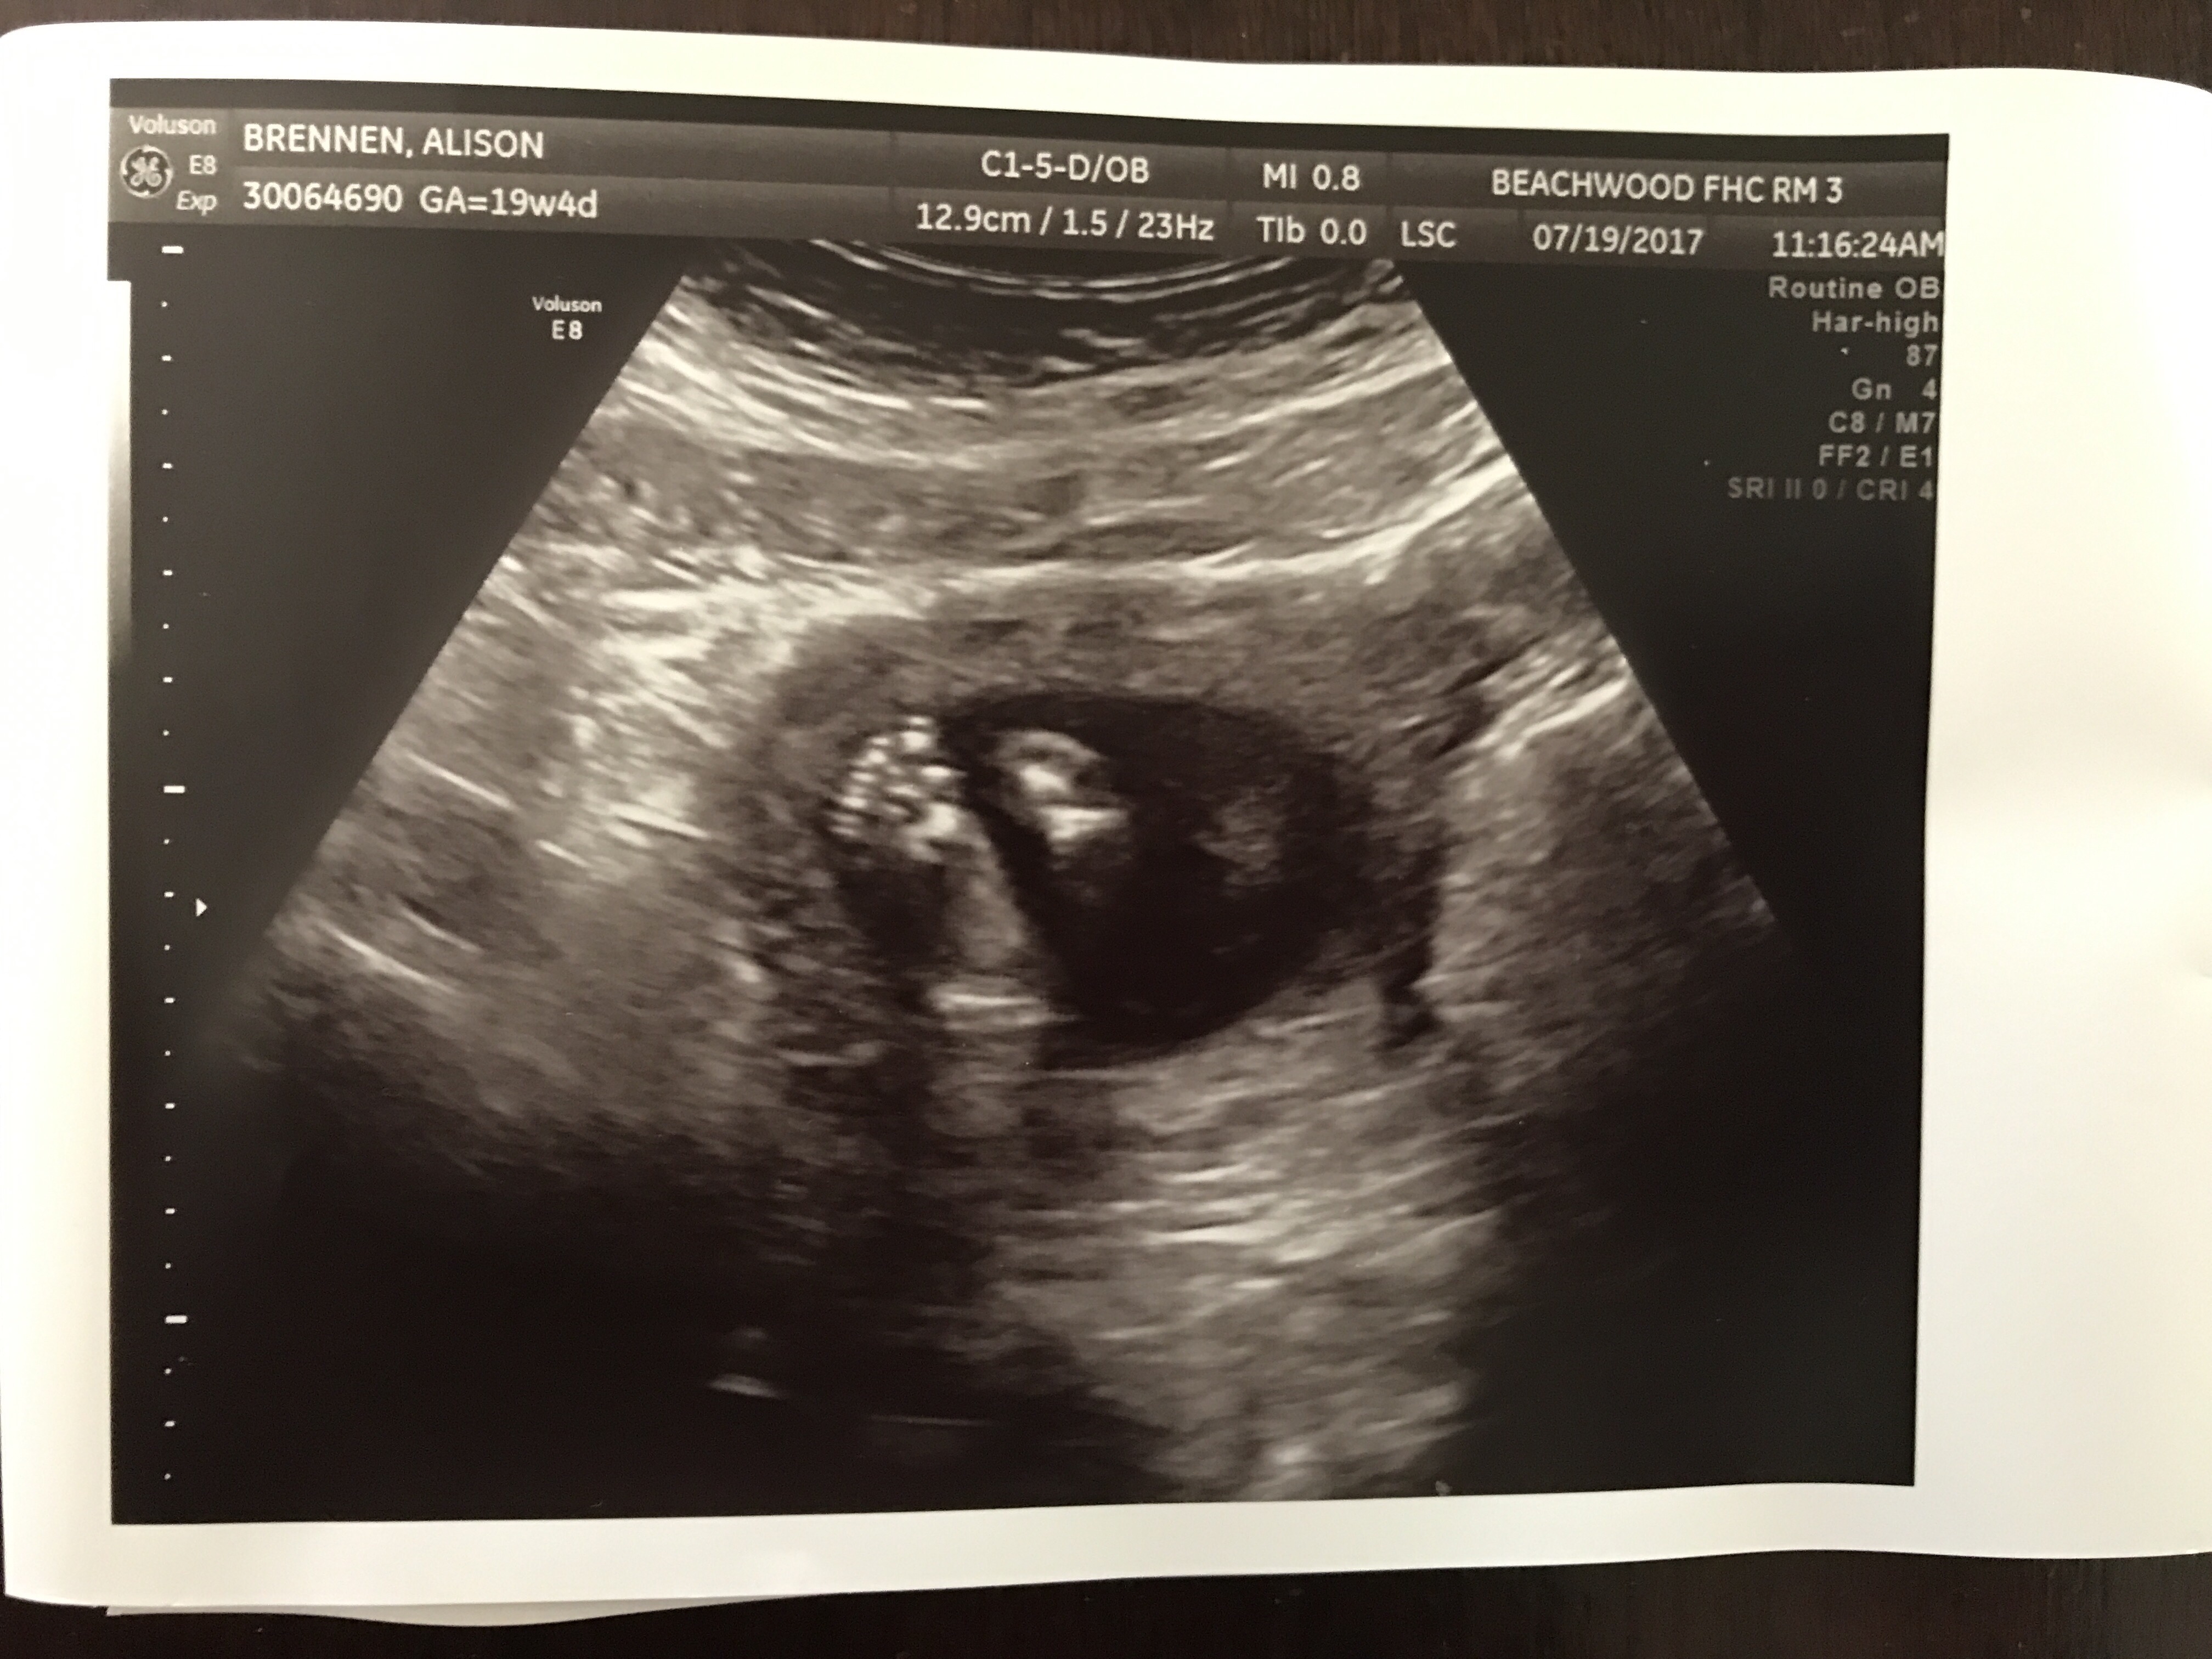

On Tuesday, we had our anatomy ultrasound and took Auntie Emmy and Grammy Ronda with us. The tech was not as intrigued as we were but we eventually wore her down and she started narrating what she was seeing. We were there for about twenty minutes so we got to see a lot – including our son’s beautiful face! (We also confirmed his gender, but I’ll save you – and him! – the pornography!) The tech and the doctor thought everything looked great – more wonderful news for us!

(Top: baby’s profile – he’s looking up; bottom: his little feet!)